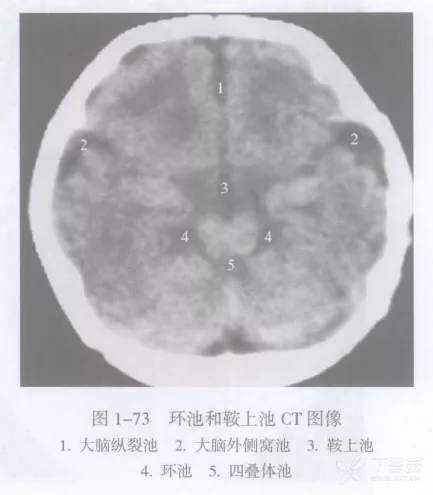

大脑纵裂池

大脑纵裂池 cistern of cerebral longitudinal fissure (interhemispheric fissure cistern)位于两侧大脑半球之间的大脑纵裂内,内有大脑镰插入,故此池分为左右两部。

该池底部绕于胼胝体周围,称为胼胝体体周池,向前下延为终板池,向后下续于大脑大静脉池。

大脑纵裂池在不同横断面上的表现各异。例如,在胼胝体以上层面中所见为大脑纵裂池全长;在胼胝体出现的层面上大脑纵裂池分为前后两段,分别位于胼胝体断面的前后方;在较低的鞍上池层面则只见大脑纵裂池前段。

大脑外侧窝池

大脑外侧窝池 cistern of lateral fossa of cerebrum 又名侧裂池,位于大脑外侧窝内。

大脑外侧窝池在横断面上的典型表现呈横置的 “Y” 形,主干伸至岛叶表面即分为前后两支,前支较短伸向前内,后支较长伸向后方。

四叠体池

四叠体池 quadrigeminal corpus cistern 又称上池 superior cistern ,居中脑四叠体后面与小脑蚓部前缘之间,两端向外连于环池翼部,向前外通环池本部。四叠体池和环池位于小脑幕切迹内,幕上或幕下的病变可经这些脑池延伸。例如,小脑幕切迹疝可使这些脑池变窄或消失。

环池

环池 ambience cistern 分本部和翼部。

鞍上池

鞍上池 suprasellar cistern 为CT 和MRI 等影像学用语。鞍上池位于蝶鞍上方,是交叉池、脚间池或桥池在轴位扫描时的共同显影。